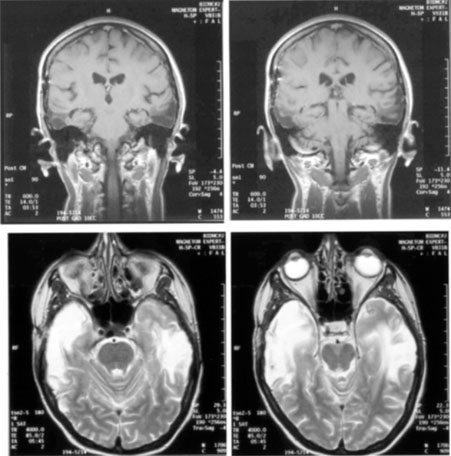

Achromatopsia in the contralateral hemifield alone can follow unilateral right or left occipital lesions (Fig. 18). Patients are typically asymptomatic until the defect is demonstrated on examination.234,235 Hemiachromatopsia is usually associated with a superior quadrantanopia;234,235,241 therefore, the color defect is only demonstrable in the remaining inferior quadrant. The preserved color vision in the ipsilateral hemifield allows normal or near-normal performance on centrally viewed tests of color vision such as pseudoisochromatic plates. The incidence of hemiachromatopsia is probably underestimated, given its asymptomatic nature and the failure of routine clinical color tests to detect its presence.

Fig. 18. Magnetic resonance imaging scan of patient with stroke causing a right hemiachromatopsia as well as partial superior quadrantanopia.